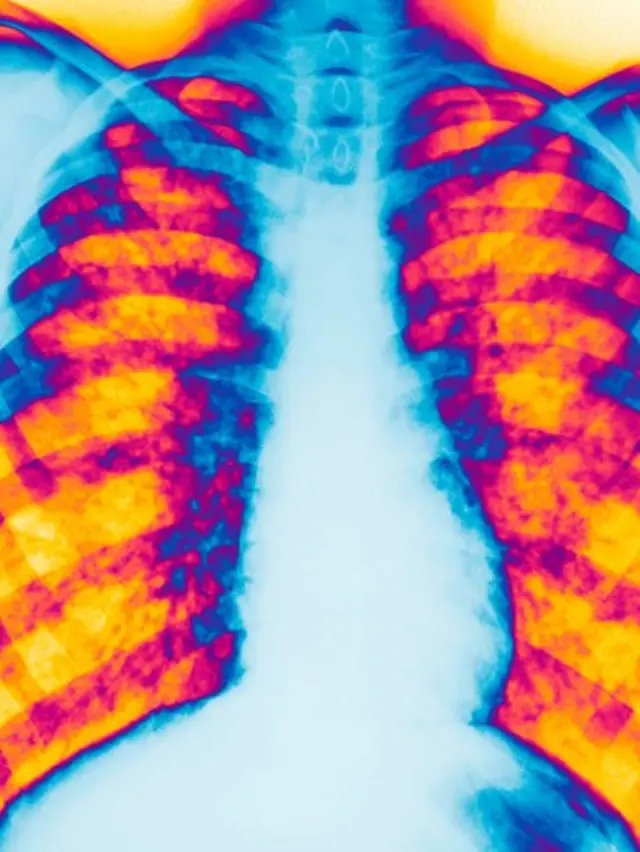

El paciente toma alrededor de 60 pastillas al día para ayudar a controlar la enfermedad, un mal genético que provoca la acumulación de flema en los pulmones, y que también puede afectar al páncreas y al tracto gastrointestinal.

Fuente de la imagen, Science Photo Library

El caso de Bauer es ejemplo de que la esperanza de vida de los pacientes con fibrosis quística ha aumentado mucho más rápidamente en Canadá que en EE.UU., según un estudio publicado en marzo en la revista médica Annals of Internal Medicine (Anales de Medicina Interna), del Colegio Estadounidense de Médicos Internistas.

Entre 2009 y 2013, los canadienses con fibrosis quística vivieron en promedio 10 años más que los estadounidenses con la misma enfermedad, debido en parte a las diferencias entre los sistemas de salud que existen en los dos países, según la investigación.